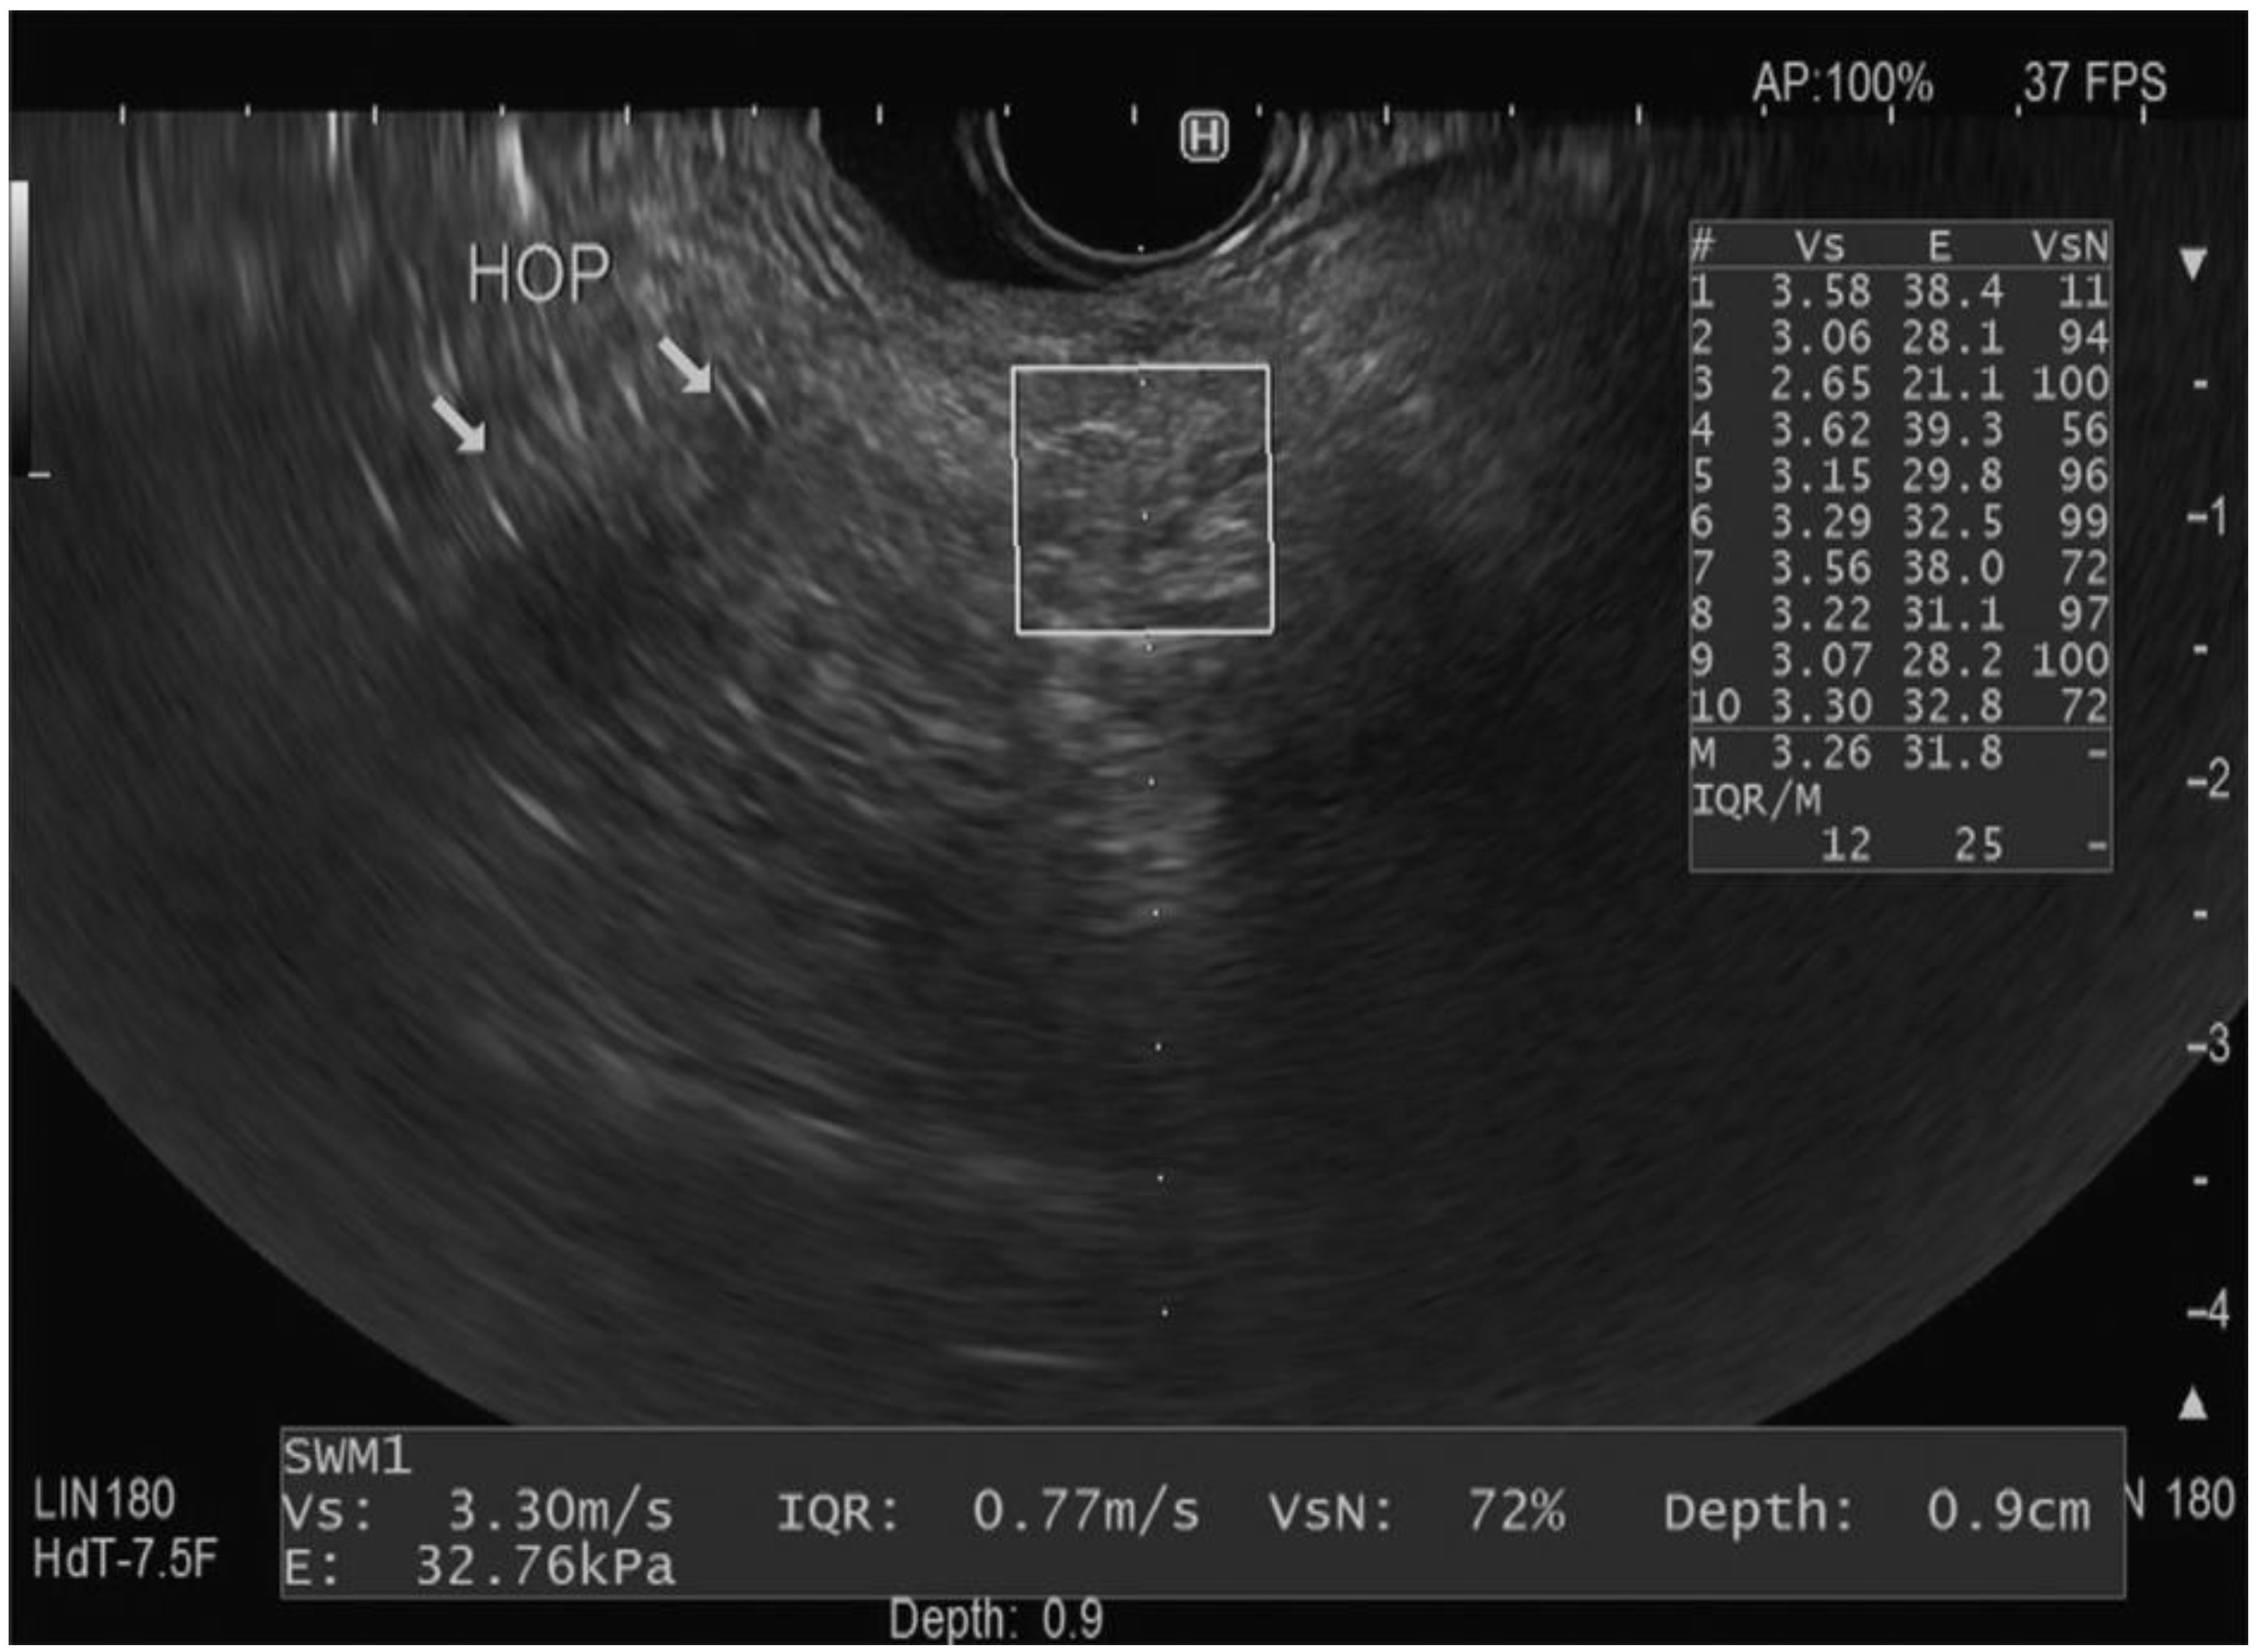

- Abboud, Y.; Kim, K.; Samaan, J.S.; Chen, C.; Lew, D.; Ghaith, J.; Caldera, W.; El Helou, M.O.; Park, K.H.; Liu, Q.; et al. Endoscopic Ultrasound Guided Shear Wave Elastography Is Safe with High Feasibility and Reproducibility When Used in the Pancreas: Findings From a Prospective Cohort. Pancreas 2023, 52, e115–e120. [Google Scholar] [CrossRef]

- Ohno, E.; Hirooka, Y.; Kawashima, H.; Ishikawa, T. Feasibility of EUS-guided shear-wave measurement: A preliminary clinical study. Endosc. Ultrasound 2019, 8, 215–216. [Google Scholar] [CrossRef]

- Ohno, E.; Hirooka, Y.; Kawashima, H.; Ishikawa, T.; Tanaka, H.; Sakai, D.; Ishizu, Y.; Kuzuya, T.; Nakamura, M.; Honda, T. Feasibility and usefulness of endoscopic ultrasonography-guided shear-wave measurement for assessment of autoimmune pancreatitis activity: A prospective exploratory study. J. Med. Ultrason. 2019, 46, 425–433. [Google Scholar] [CrossRef] [PubMed]

- Yamashita, Y.; Tanioka, K.; Kawaji, Y.; Tamura, T.; Nuta, J.; Hatamaru, K.; Itonaga, M.; Yoshida, T.; Ida, Y.; Maekita, T.; et al. Utility of Elastography with Endoscopic Ultrasonography Shear-Wave Measurement for Diagnosing Chronic Pancreatitis. Gut Liver 2020, 14, 659–664. [Google Scholar] [CrossRef]

- Ohno, E.; Kawashima, H.; Ishikawa, T.; Iida, T.; Suzuki, H.; Uetsuki, K.; Yashika, J.; Yamada, K.; Yoshikawa, M.; Gibo, N.; et al. Diagnostic performance of endoscopic ultrasonography-guided elastography for solid pancreatic lesions: Shear-wave measurements versus strain elastography with histogram analysis. Dig. Endosc. 2021, 33, 629–638. [Google Scholar] [CrossRef] [PubMed]